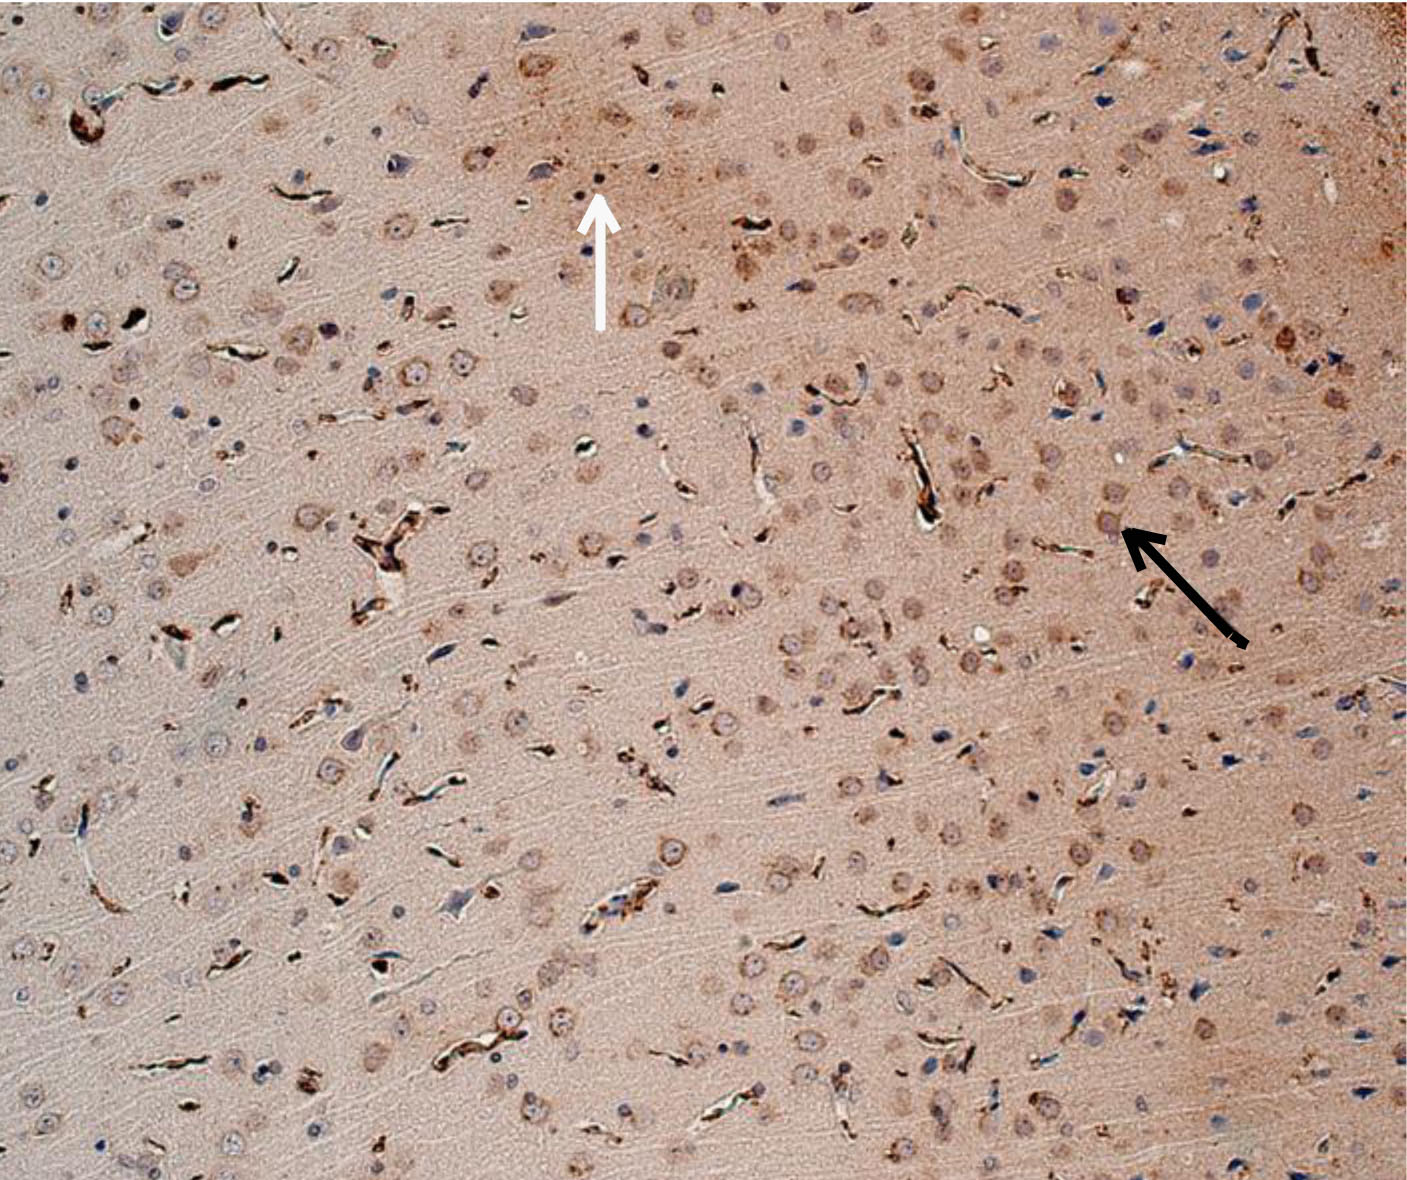

Рис. 1. Интактное животное – цитоплазматическая экспрессия ИРМ от слабой до умеренной степени. Иммуногистохимическое исследование, антитела против IL-6. Увеличение ×200. Черные стрелки – экспрессия в неповрежденных нейронах. Белые стрелки – экспрессия в нейропиле

При оценке результатов ИГХ исследования коры 19-месячных крыс без СД (интактных) была выявлена слабая равномерная экспрессия ИРМ IL-6 во всех слоях первичной и вторичной соматосенсорных областях коры головного мозга. В моторной, а также ретроспленальной коре была обнаружена цитоплазматическая экспрессия IL-6 в перикарионах нейронов от слабой до умеренной степени. У отдельных животных отмечалось наличие умеренной экспрессии IL-6 в базальных отделах коры. Преимущественно экспрессия ИРМ IL-6 определялась в цитоплазме неповрежденных нейронов, реже в нейропиле. В группе животных с экспериментальным СД1 без лечения наблюдалось увеличение выраженности экспрессии ИРМ IL-6 от умеренной до выраженной степени в сравнении с группой 19-месячных животных без СД. Характер экспрессии схож с характером экспрессии у 19-месячных животных без СД. Цитоплазматическая экспрессия ИРМ IL-6 также наблюдалась в моторной и ретроспленальной коре, локализация ИРМ IL-6 определялась в перикарионах нейронах пирамидного, внутреннего зернистого, ганглиозного слоев и в микроглии. В группах фармакокоррекции сукцикардом и аминалоном в сравнении с группой животных с СД1 без лечения наблюдалось снижение выраженности экспрессии во всех областях коры головного мозга, а в базальных отделах вплоть до исчезновения ИРМ IL-6 (рис. 1–4).